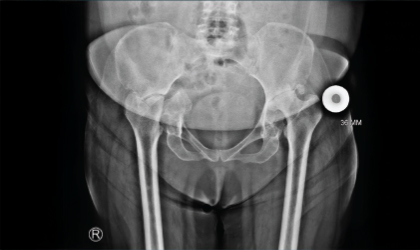

This 54 year old professor from a medical college was referred to us with severe damage to both hips and a fracture through her right side due to rheumatoid arthritis On the right side she had surgery to fix her pelvis discontinuity followed by bone grafting and a replacement. On her left side she had a replacement with an augment to build up the wall. She now back to work, and is able to do her daily chores without any restrictions.

Imaging revealed extensive bilateral hip destruction with pelvic discontinuity on the right. Her mobility and quality of life were severely affected.